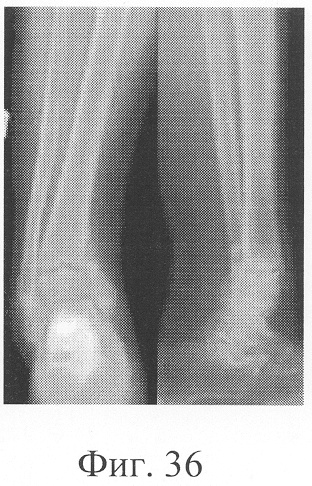

Больная П., 42 лет, поступила для оперативного лечения с диагнозом «атрофические ложные суставы обеих большеберцовых костей; сросшийся с укорочением 5 см перелом левой бедренной кости, хронический остеомиелит левой бедренной кости, фаза ремиссия; посттравматическая невропатия правого малоберцового нерва». В анамнезе – накостный, а затем дважды внеочаговый остеосинтез левой большеберцовой кости с исходом в ложный сустав; 4 операции внеочагового остеосинтеза правой большеберцовой кости, в том числе с костной пластикой; сроки фиксации в аппарате от 5 до 10 мес. Результат не достигнут: с обеих сторон сформировались ложные суставы (фиг.8-11 – клинические и фиг.12-15 – рентгенологические данные до лечения по предложенному методу).

Больной Р., 46 лет, поступил для планового оперативного лечения с диагнозом «ложный сустав правой большеберцовой кости с варусно-антекурвационной деформацией» (фиг.34-37 клинико-рентгенологические данные до операции). Предшествующее лечение перелома проводилось консервативным способом, можно отметить несостоятельность и недостаточную продолжительность иммобилизации, что является у данного пациента основным фактором в формировании ложного сустава. Из сопутствующей патологии необходимо отметить гипертоническую болезнь II ст., ИБС, атеросклеротический кардиосклероз, НК II А ст. Во время операции произведена экономная резекция фрагментов, устранение деформации в аппарате внешней фиксации, костная пластика деминерализованным костным трансплантатом, заселенным аутологичными мезенхимальными стволовыми клетками, по предложенной методике (при этом костный паз был выполнен по внутренней поверхности в области диастаза между костными фрагментами). В послеоперационном периоде дренажи удалены на 2-е сутки, швы сняты на 21 сутки в связи с развитием краевого некроза в области послеоперационной раны. Ходьба при помощи костылей с 7-х суток послеоперационного периода, дозированная нагрузка на конечность с третьего месяца после операции с учетом локализации повреждения в дистальной части большеберцовой кости (фиг.38-42 – клинические и рентгенологические данные в процессе лечения). Из осложнений необходимо отметить воспаление в области чрескостных элементов в конце периода фиксации, что купировано после снятия аппарата. Демонтаж аппарата внешней фиксации через 5,5 месяцев при клинико-рентгенологической картине сращения.